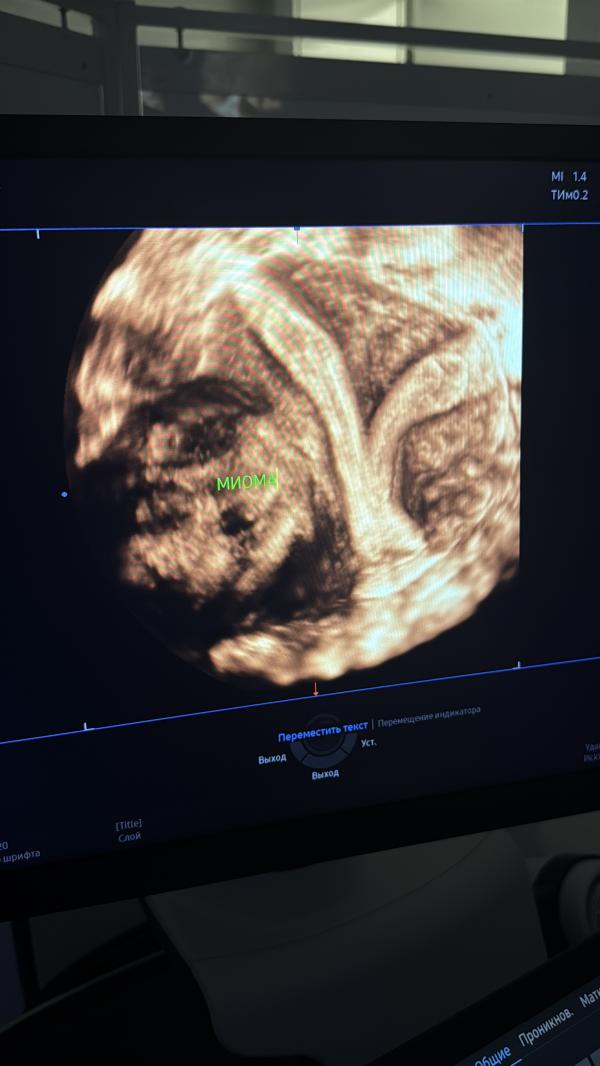

Если вы не знаете что это , я вам подскажу

Это моя матка 🙋🏻♀️

И сколько же хлопот она мне доставляет 🥲

Напоминает мне ушки зайца ( я уже и шучу , деваться иначе некуда ) 😆

Скоро у меня будет операция , в первые в моей жизни ! 💔

Будут удалять миому ,которая активно растет

А самое главное перегородку в матке , чтоб хотя бы немного её округлить , операция сложная , так как в такой матке вынести ребенка я не могу , и все это к сожалению, я узнала совсем недавно , хотя я с этим родилась , и очень мног...